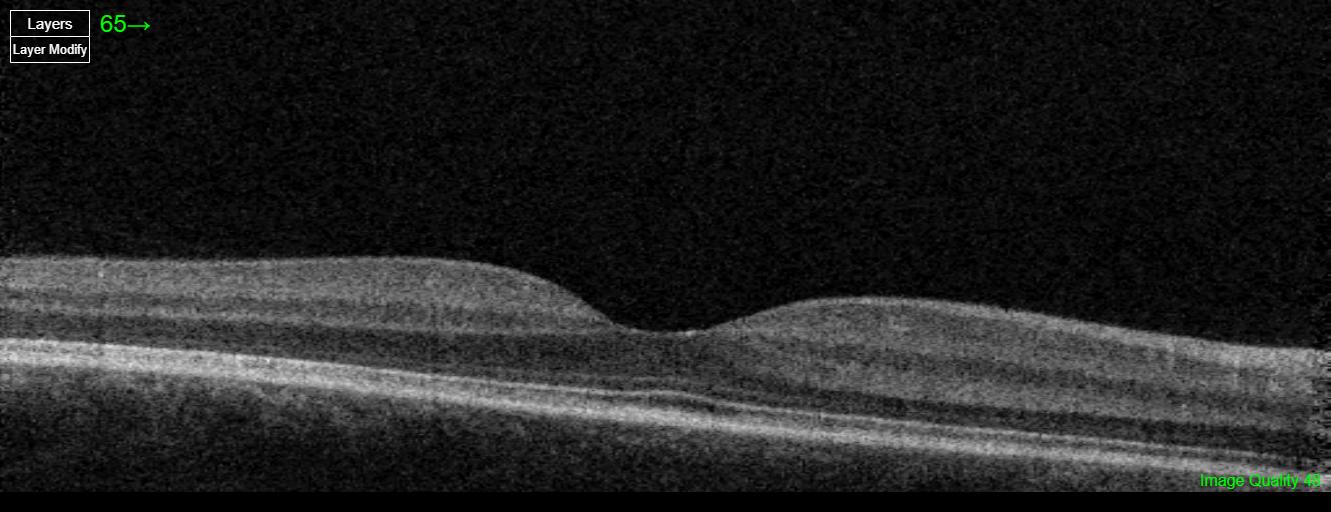

This patient’s symptoms and imaging findings are consistent with trauma-related vitreous disruption. Fundus photos show intraretinal hemorrhages, and OCT reveals slight alteration of the foveal contour. Vitreous disruption after trauma is common and may progress to posterior vitreous detachment. The patient should be advised about warning signs of retinal detachment.